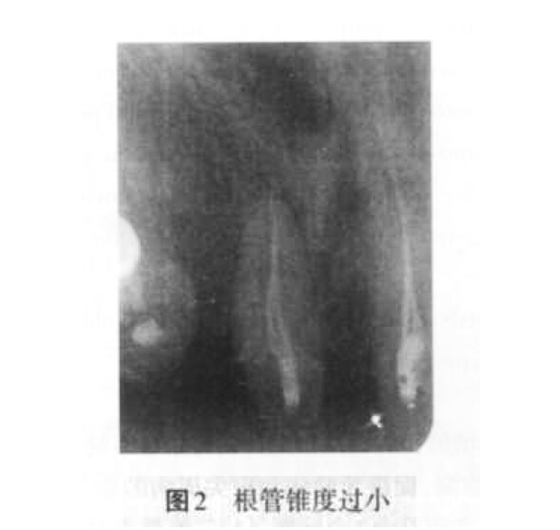

2. 1 充填不致密的原因 主要是因為根管預(yù)備不足、根管錐度過?。▓D2)、未根據(jù)患牙根管形態(tài)的特點合理選擇根充材料和技術(shù)。此外,術(shù)者操作不當(dāng)也是導(dǎo)致根充不致密的原因之一。